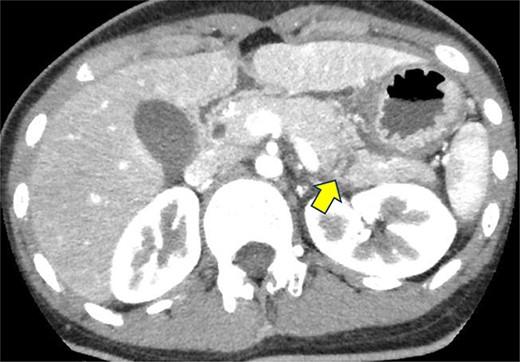

A 19-year-old woman who had fallen from a bicycle and bruised her upper left abdomen with handlebars presented to our emergency department 18 h after the injury with persistent abdominal pain. She was admitted with a diagnosis of pancreatic injury, as evidenced by elevated pancreatic amylase (P-Amy) levels (779 IU/L) and contrast-enhanced computed tomography (CT) showing a linear area with poor contrast in the pancreatic body (Fig. 1). Physical examination revealed a flat abdomen with mild tenderness in the upper left quadrant. Biochemical blood tests revealed elevated inflammatory markers; white blood cell count 10 950/μl, and C-reactive protein 0.58 mg/dl. On the fourth day, white blood cell count elevated to 21 940/μl and C-reactive protein elevated to 32.7 mg/dl. Contrast-enhanced CT revealed fluid accumulation, indicating pancreatic pseudocyst, primarily in the ventral pancreatic body and extending toward the spleen, along with edematous thickening of the adjacent stomach wall (Fig. 2).

Contrast-enhanced CT on admission. Linear areas with poor contrast in the pancreatic body and increased peripancreatic fatty tissue density were observed.